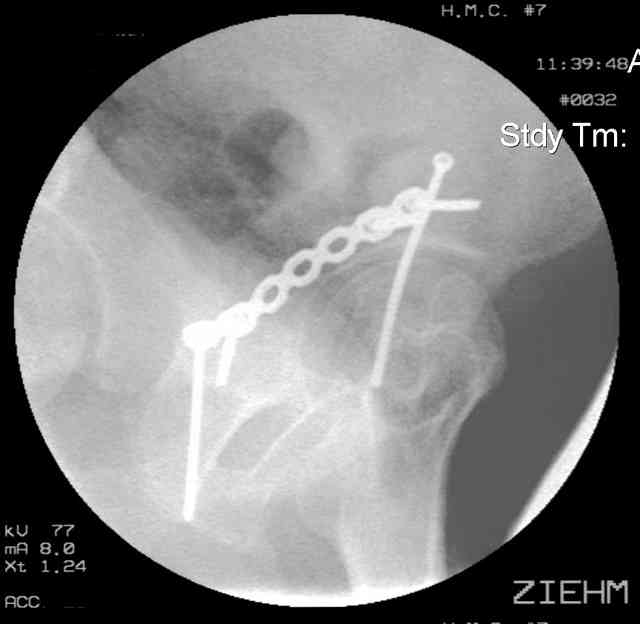

Understand that this is no simple fracture but in the same breath is very common and can be very routinely-simplistically treated without a variety of complicated and variable scenarios...keep it simple...turn him prone, clean him up, do a nice exposure, protect the nerve, remove the debris, save it and sort it out if you can, clean the fracture lines, manipulate and clamp the transverse, hold it how you choose (I'd recommend a percutaneously inserted 3.5mm antegrade medullary lag screw), remove the clamp, reduce the

small or impacted fragments to the head, reduce the wall, and support the wall and transverse with a balanced 3.5mm contoured reconstruction plate.

I'll include a few images of a similar injury in a similarly large male patient. This patient "showed up" in our ER c/o hip pain 2 months after being treated in the lateral position, without a quality reduction, without an anterior column transverse supporting implant, with an unbalanced plate applied too medially, with insufficient caudal segment fixation...it took over 8 hours and a 3+ l blood loss to debride the callus from front then

back, excise the HO, release his sciatic nerve, reduce the head-transverse-wall, and fix it...and now it's a staging procedure.